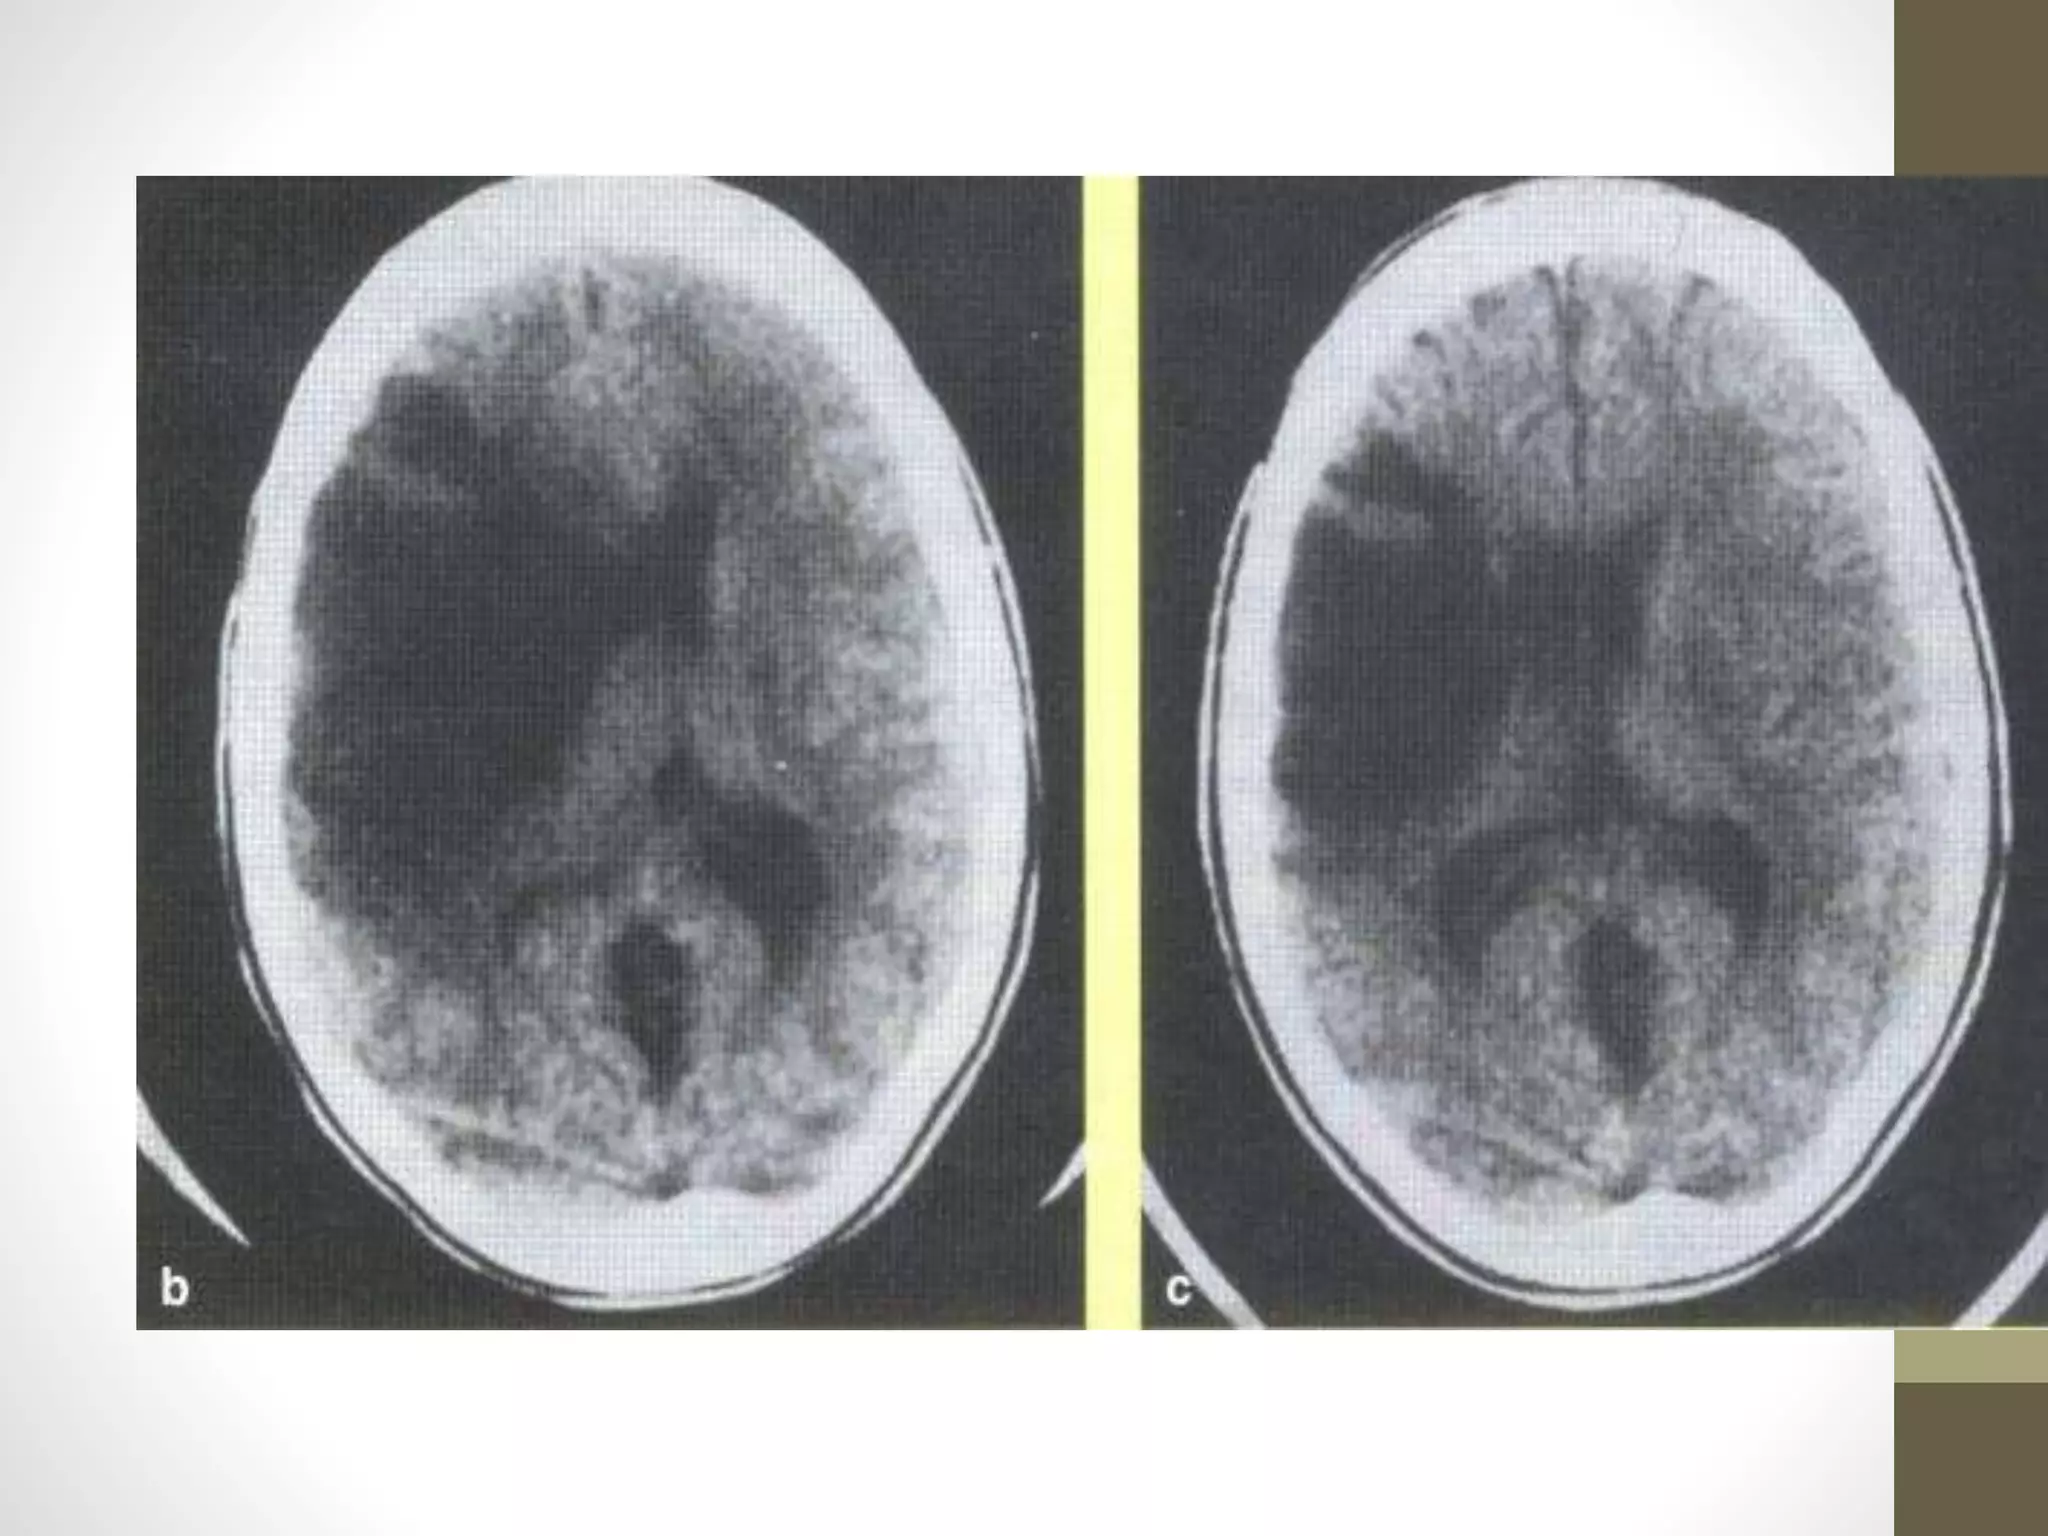

Acute

subarachnoid

hemorrhage

Diffuse areas of white

(hyperdense) images

Blood visible in

ventricles

and multiple areas on

surface of brain

Acute subarachnoid hemorrhage Diffuse areas ofwhite (hyperdense) images Blood visible in ventricles and multiple areas on surface of brain